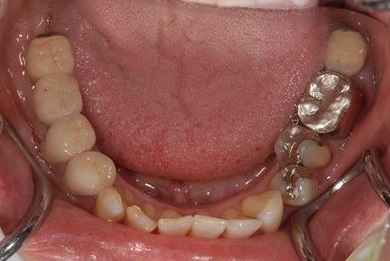

インプラント治療+セラミック治療

| 性別/年齢 | 女性 / 47歳 | ||||||||||||||||||||||||||||||||

| 主訴 | 前歯の黄ばみが気になる。 | ||||||||||||||||||||||||||||||||

| 治療方針 | インプラント・セラミック治療にて、機能的・審美的回復を行う。 | ||||||||||||||||||||||||||||||||

| 治療内容 | インプラント3本、ジルコニアフレームオールセラミッククラウン7本(ジルコニア用土台1本)、メタルボンドセラミッククラウン3本(メタルボンド用土台3本)、ハイブリッドセラミッククラウン3本、ハイブリッドセラミックインレー3本 | ||||||||||||||||||||||||||||||||